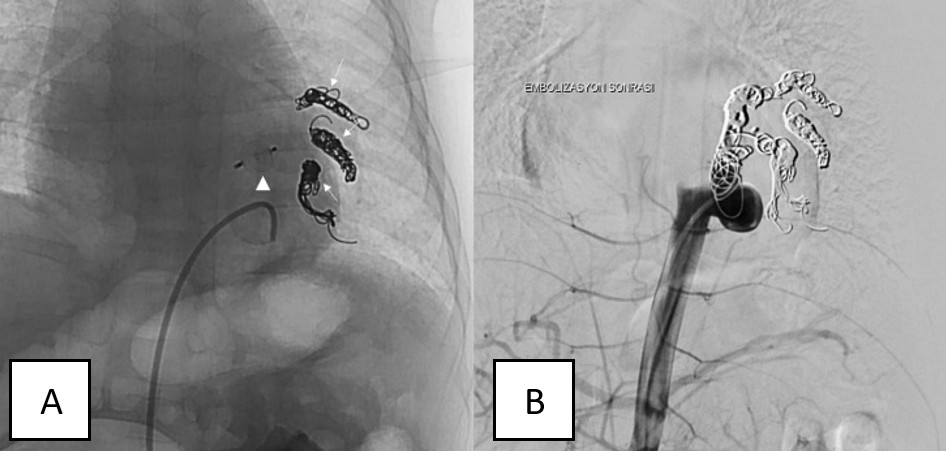

To confirm the diagnosis and exclude arteriovenous malformation, digital subtraction angiography (DSA) was performed (Figure 4). The DSA findings were consistent with the CT findings, and the aberrant branches were embolized with coils. The primary aberrant systemic artery, measuring 6.6 mm in its proximal segment, was occluded with an Amplatzer Vascular Plug, effectively terminating the aberrant arterial supply (Figure 5). No complications were observed during a 7-month follow-up period.